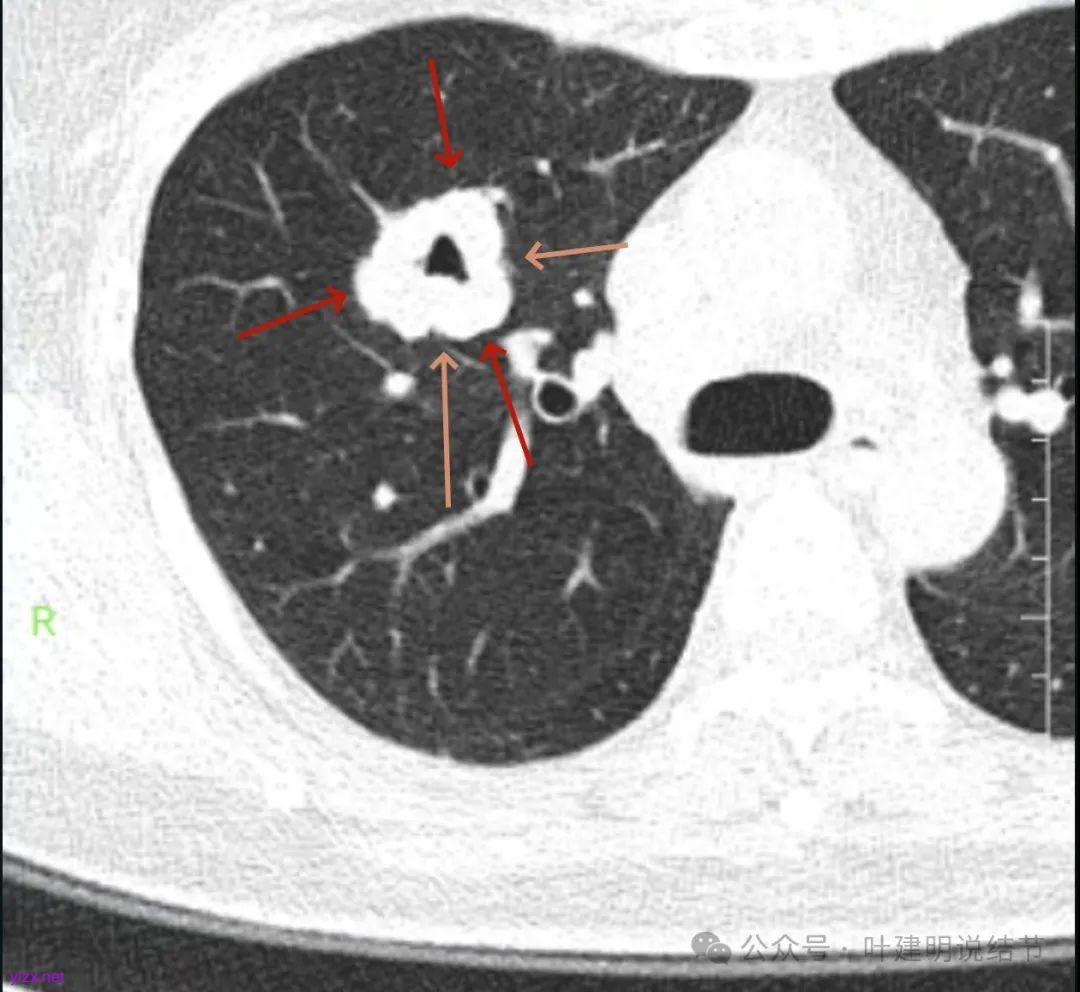

影像展示与分析:

腔静脉旁明显肿大淋巴结。

你的右上叶这个病灶基本上肯定是肺癌,要尽快处理。从影像上看有以下特点:1、整体轮廓清楚,不似普通炎症的周围有晕或阻塞性改变;2、边缘明显的浅分叶,总体上的感觉膨胀性明显,不管哪个层面看上去都是鼓鼓的;3、边缘区域有磨玻璃成分而且也是分叶状的;4、部分层面见血管进入;5、空腔病灶的壁厚薄不均,内壁不光滑。我考虑中低分化肺癌,由于腔静脉旁有明显肿大淋巴结,需要进一步完善增强CT以及PET-CT检查以明确有无远处转移,是否仍可手术治疗(从病灶本身来说是可以肺叶切除治疗的)。要尽快处理。意见供参考!